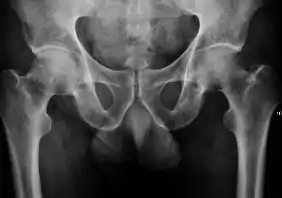

Projectional radiography ("X-ray") is the first imaging technique of choice in hip pain, not only in older people with suspected osteoarthritis but also in young people without any such suspicion. In this case plain radiography allows categorization as normal hip or dysplastic hip, or with impingement signs, pincer, cam, or a combination of both.[1]

Projectional radiography ("X-ray") is currently useful not only in older people in whom osteoarthritis of the hip is suspected but also in younger people without osteoarthritis, who are being evaluated for femoroacetabular impingement (FAI) or hip dysplasia.[1]

Plain radiography allows us to categorize the hip as normal or dysplastic or with impingement signs (pincer, cam, or a combination of both). Besides these, pathologic processes like osteoarthritis, inflammatory diseases, infection, or tumors can also be identified (Figure 1).[1]

Figure 1.